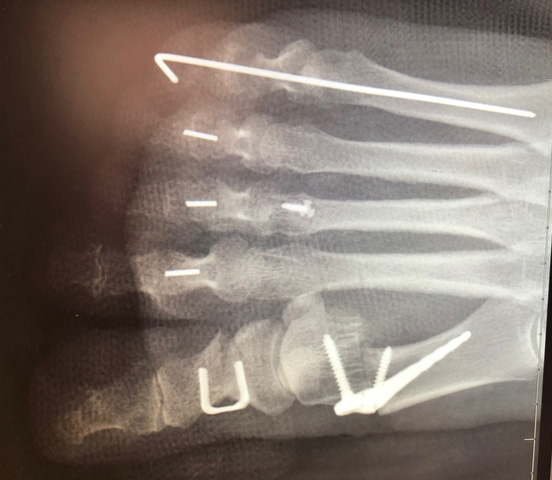

Figure 1 Vector™ Hammertoe Correction System depicts a postoperative radiograph of three hammertoe fusions with the PEEK-OPTIMA HA Enhanced PIPJ fusion devices and one fusion with a K-wire for comparison

Figure 2 PIPJ arthrodesis of 2nd, 3rd, and 4th ray using the Vector™ Hammertoe Correction System manufactured from PEEK-OPTIMA™ HA Enhanced (right). The visible metallic component is a patented tantalum structural encoded identifier for Unique Device Identification (UDI). Images provided courtesy of Nvision Biomedical Technologies. ©Nvision Biomedical Technologies.